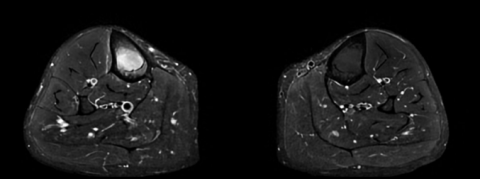

Séquence axiale.png

Séquence axiale 2.png

Séquence axiale DP FS montrant un oedème médullaire

osseux avec épaississement cortical.